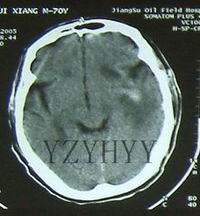

影像學檢查顱內占位性病變,如病變較小,又位於非重要功能區,臨床上可無症狀。若病變位於重要的腦功能區或病變範圍較大,臨床常出現顱壓增高的症狀(如頭痛、噁心、嘔吐等)和局灶性的神經體徵。較大的占位性病變,造成顱壓過高,壓迫腦組織,可造成肢體癱瘓,乃至形成腦疝。腦疝是危及患者生命的徵象,也是顱內占位性病變最嚴重的後果。

顱內占位性病變,常可通過影象學檢查獲得確診。影象學檢查包括頭顱CT掃描、核磁共振檢查及腦血管造影等。現代影象學檢查可顯示占位性病變的位置、大小、形態、數目,還能觀察到病變內部是否有囊變、壞死、鈣化、出血等。腦血管造影是根據血管的部位、形態的改變、循環時間的改變以及病理血管的出現等,間接了解病變的位置、大致形態、含血管是否豐富等。